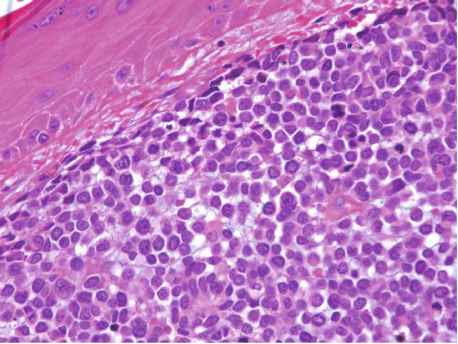

Merkel cell carcinoma (MCC) is a rare and aggressive form of skin cancer that usually appears as a painless, firm, shiny red, purple or pink nodule on sun exposed areas of skin. It arises from Merkel cells in the skin which are neuroendocrine cells that may be involved in light touch sensation and proprioception. MCC often occurs in older adults and people with weakened immune systems.The Merkel Cell Carcinoma Market comprises of drug therapies including chemotherapy, surgery, radiation therapy and immunotherapy that are used in the treatment of MCC.